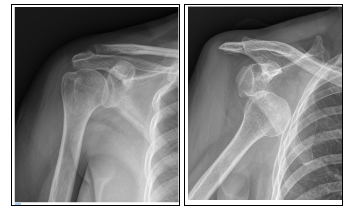

1) 어깨 탈구

어깨 탈구의 경우에는 어깨가 움직일 수 있는 범위 이상으로 팔이 꺾이거나 무리한 운동으로 인해서 발생한다. 심한 통증이 발생하기 때문에 병원에 방문하여 관절을 맞추는 치료를 받아야 한다. 하지만 한 번 탈구가 되면 습관성 탈구로 이어질 수 있기 때문에 항상 조심해야 한다.